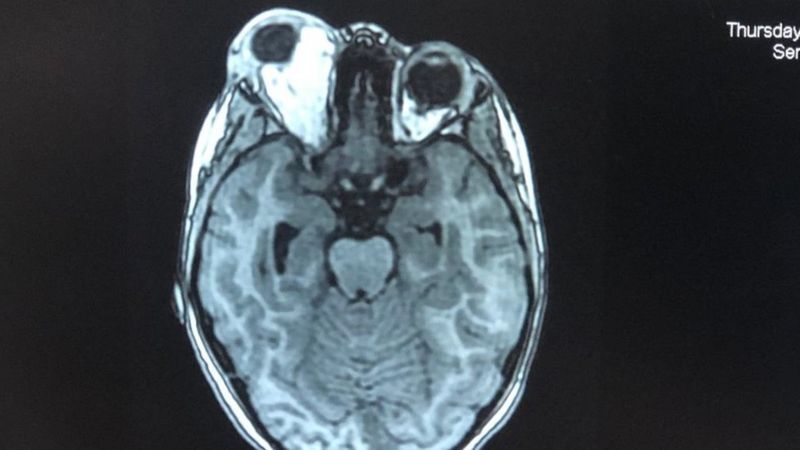

"Yasmin fue hospitalizada y le hicieron radiografías, tomografías y resonancias magnéticas mientras los médicos decidían qué hacer", resume.

Una de las tomografías mostró cómo el ojo derecho de Yasmin (la mancha blanca a la izquierda en la imagen) sobresalía.